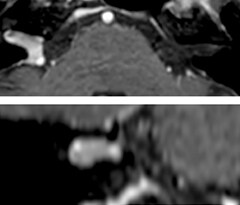

A two year follow-up scan of a CPA meningioma using both Ingenia 3.0T without CS and Ingenia Elition 3.0T with Compressed SENSE allows for a nice comparison to demonstrate the protocol improvements achieved on the Elition: 3D FLAIR has a shortened scan time, improved SNR and still the same spatial resolution. BrainView (3D T1 TSE) has improved spatial resolution and SNR with shortened scan time. For 3D T2 Drive the spatial resolution has been improved. 3D THRIVE used to have an interpolated 0.8 mm slice thickness, but true thickness at 1.6 mm, so that axial slices displayed a decent quality, but reformats were suboptimal. Compressed SENSE is used on Elition to improve spatial resolution and reduce the non-interpolated slice thickness to allow smoothly reformatted images. Total scan time (adding SmartBrain and an additional b2000 diffusion) was 13:19 on Ingenia, and is now reduced to 10:42 on Ingenia Elition.

Ingenia 3.0T (without Compressed SENSE)

3D FLAIR 1.0 x 1.0 x 1.0 mm* 4:24 min.

3D TSE T1w 1.0 x 1.0 x 1.2 mm* 2:40 min.

3D T2w Drive 0.8 x 0.8 x 1.0 mm* 3:05 min.

3D T1w THRIVE 0.8 x 0.8 x 1.6 mm* 1:30 min.

Ingenia Elition 3.0T with Compressed SENSE

3D FLAIR 1.0 x 1.0 x 1.0 mm* 2:50 min.

3D TSE T1w 1.0 x 1.0 x 1.0 mm* 2:10 min.

3D T2w Drive 0.7 x 0.7 x 0.7 mm* 2:52 min.

3D T1w THRIVE 0.7 x 0.7 x 0.8 mm* 1:30 min.

*true voxel size, without interpolation

The 3D TSE T1w black blood MSDE sequence with fat suppression has an isotropic 0.8 mm voxel size and sagittal oblique and axial reformats are made. The images show superficial temporal artery thickening and peri-arterial fat infiltration. The 3D TSE PDw black blood MSDE with fat suppression has 0.55 mm isotropic voxels. The images shows focal involvement of the frontal branch of the superficial temporal artery.